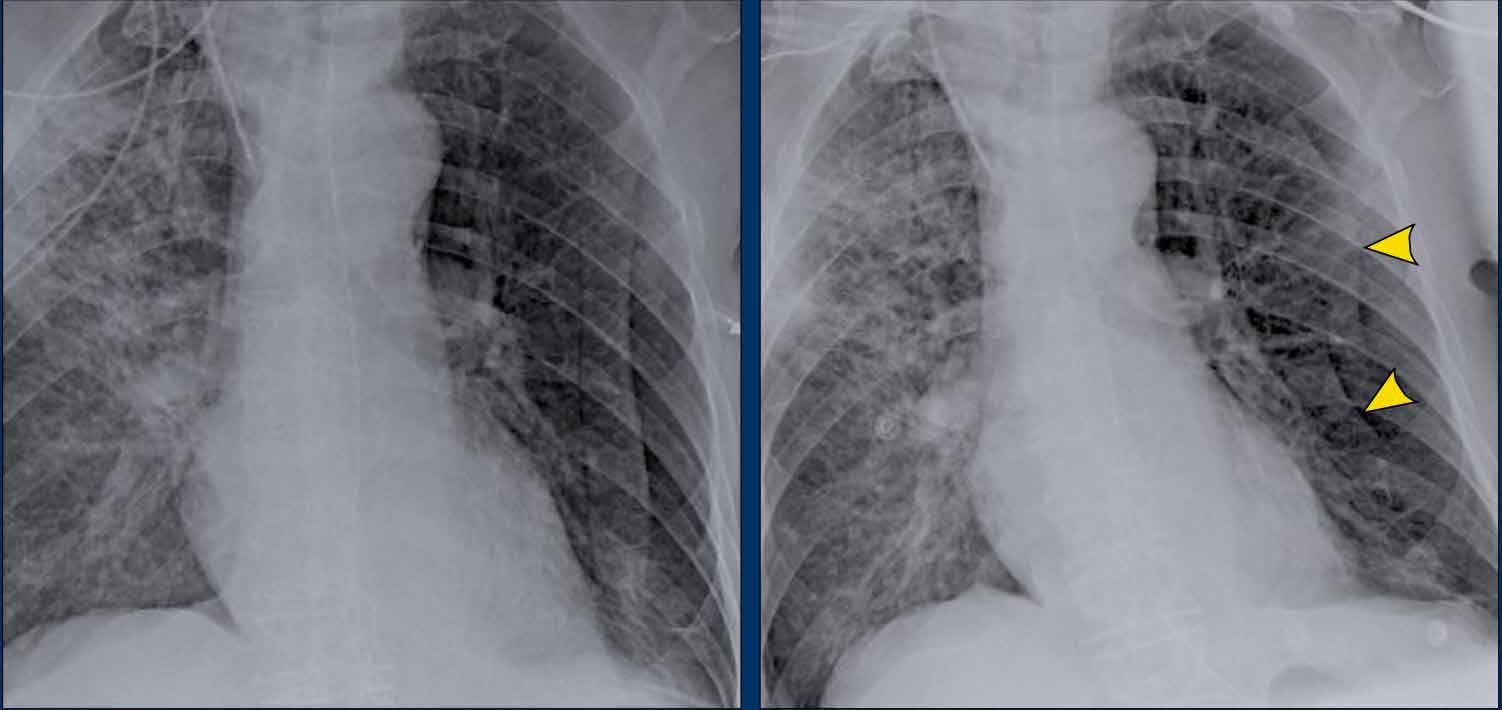

Displacement of the Azygoesophageal Line (1) – Hiatal hernia

A hiatal hernia (arrowheads) is the most common cause of displacement of the azygoesophageal line as seen on the PA-view.

Notice the air within the hernia on the lateral view (black arrow).